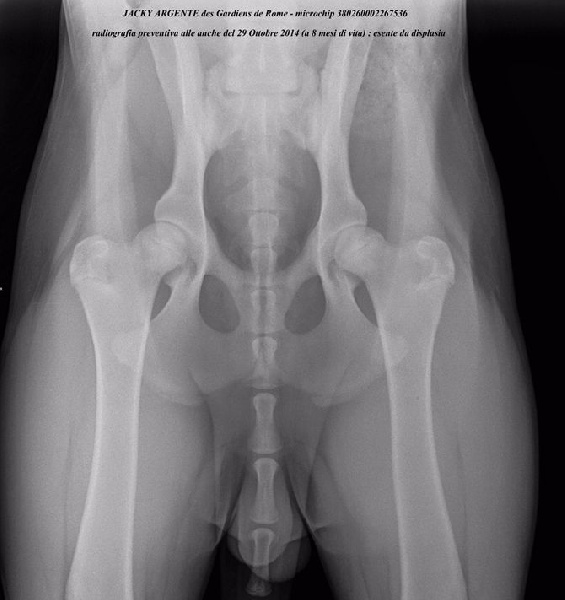

CH. Jacky argenté Des Gardiens De Rome

| Puce | 380260002267536 |